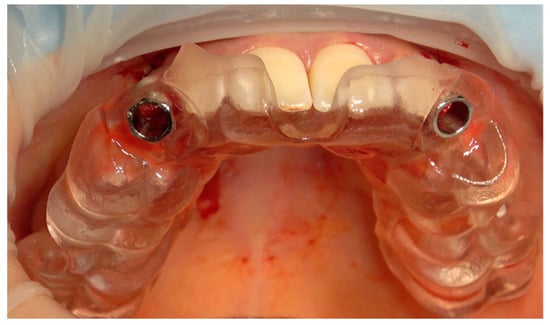

2.3. Surgical and Prosthetic Workflow